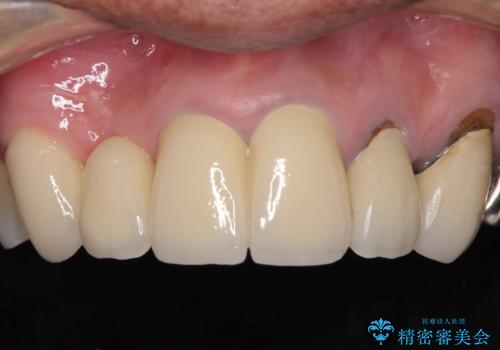

欠けてしまった前歯のブリッジをオールセラミックブリッジへ

- 前歯のブリッジのセラミックが欠けてしまい、作り直したいとのことで来院された患者様です。

犬歯はブリッジの中で虫歯が進行していたため、根管治療からやり直しをした後、オールセラミックブリッジにて補綴することとしました。

歯肉が少し退縮していたため、補綴治療のやり直しにより歯が少し長く見えるようになりましたが、自然な口元に仕上がり、患者様には大変満足していただきました。